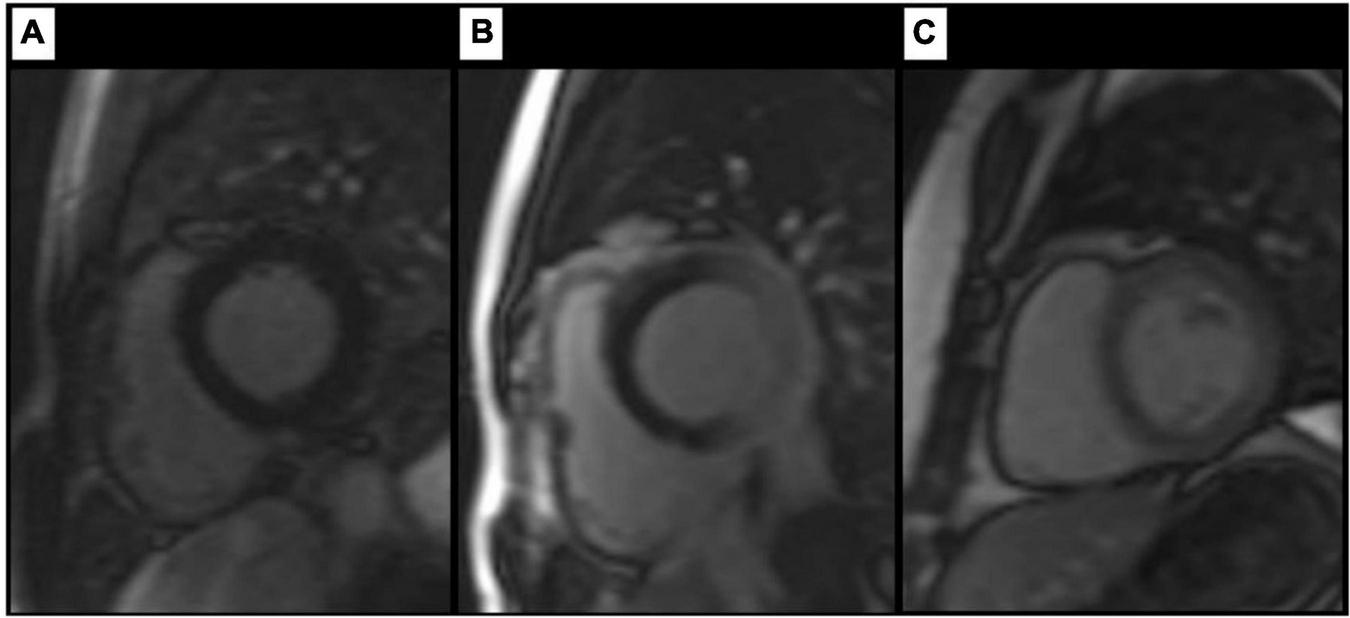

FIGURE 2

Findings on LGE images. Artefact-free images of a healthy control (A). Columns (B,C) show examples of artefacts in patients with LBBB each resulting in an amorphous signal increase within the myocardium (white arrow heads) without a correlate in an intersecting plane. Examples of true LGE (white arrows) in patients with LBBB are shown in columns (D,E). Here, both planes show an intramyocardial (septum) and subendocardial (free wall) signal increase (D) respectively a typical subepicardial signal increase (E). The red dashed lines depict the respective intersection of both planes shown.